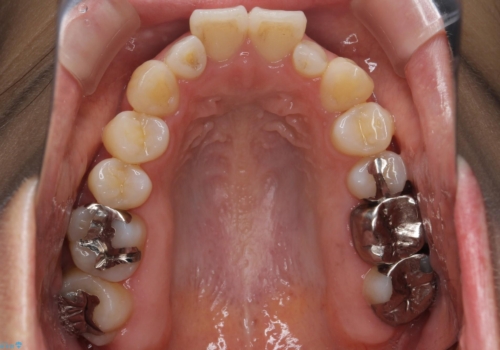

矮小歯 セラミッククラウンで綺麗に 30代女性

全顎的に歯並びにがたつきがあり、上の側切歯(上顎両側2)は生まれつき小さい歯(矮小歯)でした。

矯正治療後、矮小歯をセラミッククラウンにより理想的な歯の大きさに仕上げました。